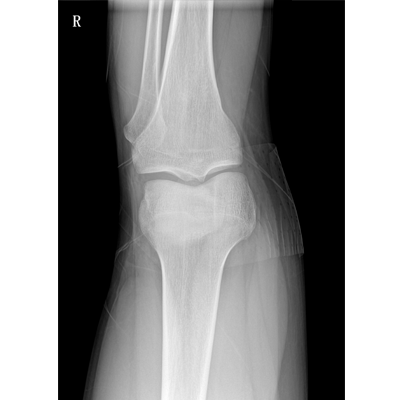

用于影像科、急診室、病房、ICU、手術(shù)室等多場(chǎng)景應(yīng)用。

● 數(shù)字化無(wú)線平板成像,操作簡(jiǎn)便,成像質(zhì)量高